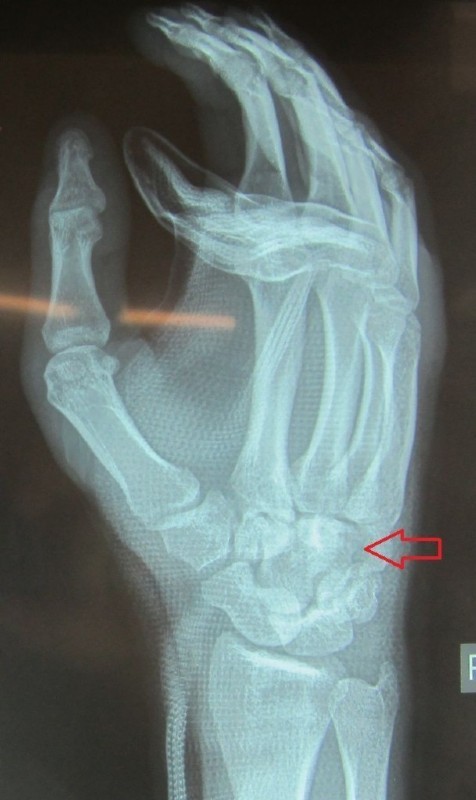

Fracture of the fifth metacarpal bone.

This young man fell off the skateboard and broke his fifth metacarpal. The conducted cast immobilization in the emergency hospital was found to be ineffective, because the bone was flexed too much.